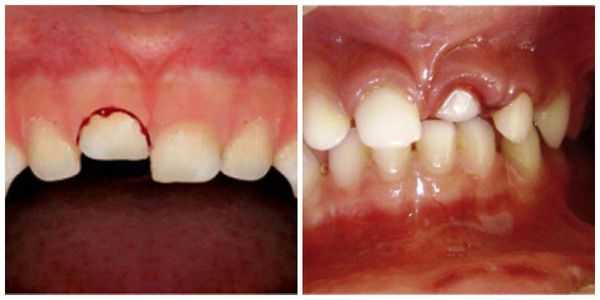

- Вколоченный вывих : пациент чувствует постоянную боль, усиливающуюся при давлении, жевании, смыкании челюстей; при пальпации десны появляется её гиперемия (покраснение) и отёчность; возникает незначительное кровотечение из места травмы. Что интересно, при перкуссии (постукивании) травмированного зуба человек не ощущает болевых ощущений и дискомфорта. При визуальном осмотре заметно укорочение зуба или же он полностью "спрятан" в лунке, при этом неподвижен.

Вколоченный вывих — это травма считается наиболее неблагоприятной. Тело зуба под воздействием большой давящей силы погружается в ткани челюсти (он входит глубоко в лунку) и корень внедряется вглубь альвеолярного отростка и тела челюсти. Для вколоченного вывиха также характерен полный разрыв волокон периодонта. Крайне редко некоторая их часть сохраняет свою непрерывность, но существенно растягивается и надрывается. Сосудисто-нервный пучок, как правило, разрывается. Из-за внедрения более широкой части зуба в более узкую происходит деформация стенок альвеолы: они раздвигаются и ломаются. Данный вид вывиха иногда сопровождается поворотом зуба вокруг оси, смещением в вестибулярном или оральном направлении. Особенно это касается верхних зубов, когда вследствие вывиха может произойти повреждение носовых (гайморовых) пазух.

Лечение вколоченного вывиха представляет определённые трудности.

Можно придерживаться выжидательной тактики, направленной на самостоятельное выдвижение травмированного зуба. Чаще всего данная методика применяется при вколоченных вывихах временных резцов: в данном случае выдвижению зуба способствует дальнейшее формирование корня зуба, если зона роста зуба сохранилась.

Первые признаки самопроизвольного выдвижения зуба возможно увидеть через неделю-полторы после вывиха, но иногда сроки увеличиваются до четырёх-шести недель.

При появлении признаков острого воспалительного процесса необходимо эндодонтически пролечить зуб. Резорбция корня в случае вколоченного вывиха также возможна, но она менее объёмна, чем при реплантации.